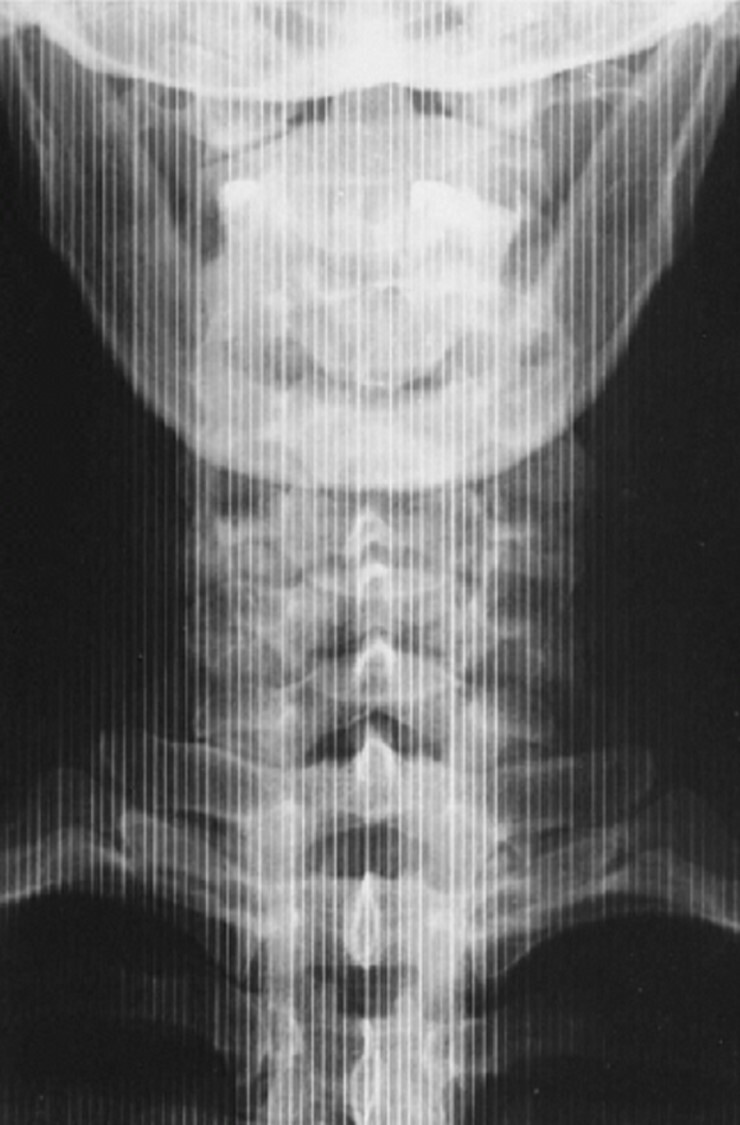

The attached image was obtained on a CR imaging system in the table bucky, using a grid frequency of 80 lines/cm and processed with a laser read out running perpendicular to the grid lines. The x-ray tube was centered, in focus and the gird was properly aligned.

What is the name of the alternating dark and light line artifact seen throughout the image?

A

Moire’ Pattern due to Aliasing

Would this artifact have occurred during image processing or image acquisition?

Image processing

State the cause of the artefact.

The sampling frequency/rate of the laser was less than double the desired maximum spatial frequency.